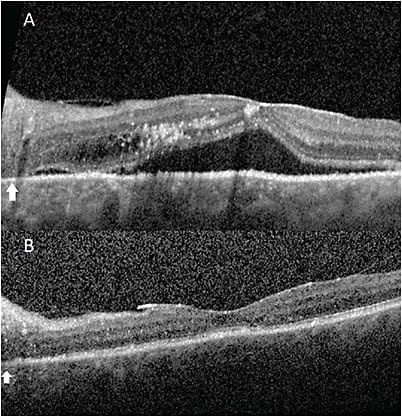

Fundus exam (Figure 1a) of the left eye revealed a serous macular detachment involving the fovea with drusen and exudates, with 360° annular shallow ciliochoroidal detachments anterior to the equator seen on indirect ophthalmoscopy. B-scan ultrasonography confirmed these detachments, with less than 1 mm average height. Fundus autofluorescence (Figure 1b) of the left eye showed a hypofluorescent gravity track emanating from the nerve, with fluorescein angiography (Figure 1c) demonstrating similar findings with hyperfluorescence at the borders. Two additional foci of peripapillary stippled hyperfluorescence and temporal crescent staining were also noted on fluorescein angiography. Indocyanine green angiography (Figure 1d) was unremarkable. Optical coherence tomography (OCT) revealed a pigment epithelial detachment (PED) in the peripapillary retina with subretinal fluid involving the fovea and accompanying intraretinal fluid and exudates (Figure 2a). The choroid was also noted to be very thick with slight choroidal folds, and a temporal crescent with outer retinal atrophy was present in the peripapillary retina.

After failing medical treatment, the patient elected to proceed with surgical intervention. Partial thickness scleral windows 5 mm x 5 mm wide with a sclerostomy were created in all four quadrants without complication. The sclera was noted to be abnormally thick during lamellar dissection, consistent with UES. No complications were noted postoperatively, and all subretinal fluid (Figure 2b) and ciliochoroidal effusions were resolved two months after surgery, with BCVA of 20/25.